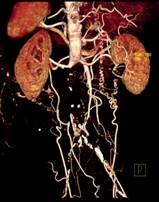

脑血管畸形CTA ,大血管成像:动态容积成像实现大范围动态血管检查